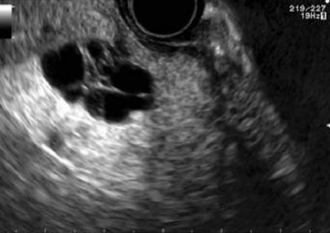

Describe this image

US guided FNA of a pancreatic tumor located in the head of the pancreas (based on landmarks)